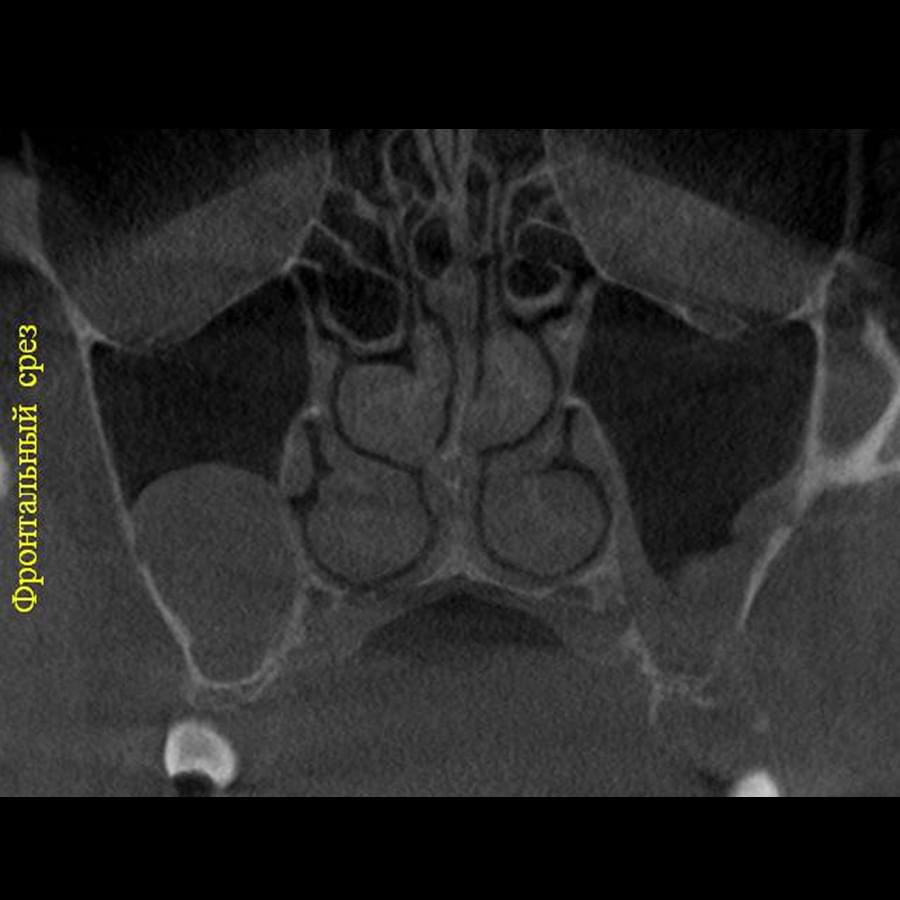

Отримайте вичерпну інформацію про стан ЛОР-органів завдяки надточній діагностиці на апараті

PLANMECA. Наші знімки дозволяють детально візуалізувати всі групи навколоносових синусів,

структури остіомеатального комплексу та анатомію носової перегородки.

Ми надаємо не просто знімок, а повний діагностичний сервіс:

Детальний опис: Кожне дослідження супроводжується професійним висновком лікаря-рентгенолога

з описом виявлених патологій (кісти, поліпи, сторонні тіла, рівень рідини, потовщення

слизової).

Зручна візуалізація: Можливість перегляду структур у будь-якій проекції (аксіальній,

корональній, сагітальній) для точної локалізації запального процесу.